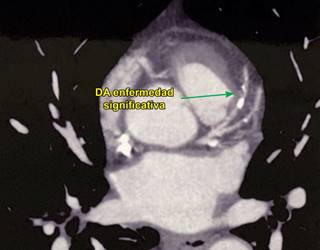

Se solicitó una placa de tórax, que mostró prominencia del botón aórtico (Figura 1).

Se realizó una TAC contrastada, con la cual se observó una variante anatómica: origen aberrante de la subclavia derecha. Se obtuvo calcio coronario en 130 UA. Se llevó a cabo una aortografía, que reveló un origen único de ambas carótidas, origen independiente de la subclavia izquierda y sobre la aorta torácica descendente, un trayecto ectásico hacia la subclavia derecha, lo que confirmó la presencia del divertículo de Kommerell. La coronariografía dejó ver enfermedad arterial coronaria severa de un vaso, con oclusión de 30% del tronco coronario izquierdo, lesión ateromatosa de la DA con oclusión proximal de 90% y media de 100%, compatible con oclusión crónica total, lo que condicionaba cardiopatía isquémica crónica (Figuras 2 a 5).

Figura 3: Tomografía axial computarizada del tórax que muestra la obstrucción significativa en la arteria coronaria descendente anterior.